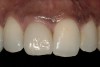

From a clinical perspective, the primary challenge was the development of an esthetic emergence of the dental implant-supported crown restoration. Maintenance of the soft-tissue dimensions, therefore, was critical to the treatment success. In an effort to optimally maintain the ridge form, a connective tissue graft harvested from the palate39,40 was placed over the collagen membrane to augment the soft tissues. Then, the buccal flap was advanced to achieve primary closure. Postoperative healing proceeded uneventfully. The overlying soft tissue exhibited rapid clinical closure and healed with minimal evidence of the surgical procedure. The clinical outcome was also consistent with development of the desired ridge form. Cone-beam computed tomography imaging revealed an alveolar ridge form that was optimal for implant placement at 5 months post-treatment. The radiographic density of the augmented region was similar to the adjacent native bone, with no discernable interface between native and apparent new bone, consistent with integration and remodeling. Surgical re-entry for implant placement revealed the optimal ridge form (Figure 6 ). The implant was allowed to integrate for 5 months prior to the healing abutment placement and interim restoration. The overcontoured soft tissues enabled surgical sculpting to achieve the desired contour for the restorative emergence. A highly acceptable esthetic result was achieved. With preservation of the marginal and papillary gingival contours (Figure 7 and Figure 8 ); the radiographic presentation was consistent with normal bone remodeling and implant integration.

Figure 7  Esthetic result achieved at the provisional stage of restoration.

Figure 7